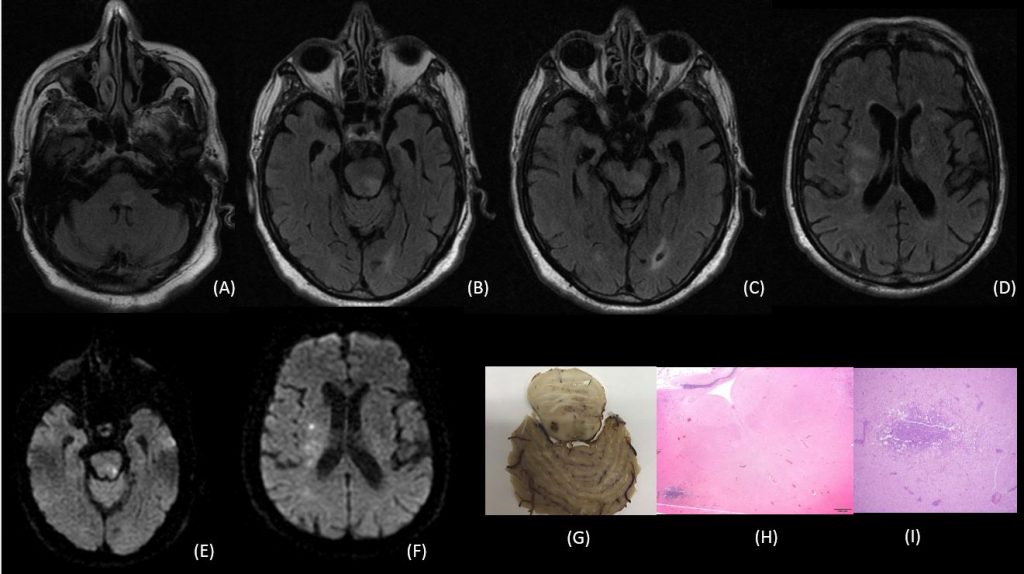

Figuras A, B, C y D son secuencias axiales potenciadas en FLAIR, en las que se identifica hiperintensidad en la región dorsal del bulbo y protuberancia (suelo del IV ventrículo) , que se extiende a la al mesencéfalo y sustancia blanca periventricular supratentorial.

Figuras E y F son secuencia de difusión, en que existe focos de restricción a la difusión en la región dorsolateral izquierda de la protuberancia y sustancia blanca periventricular derecha.

Figura G. Corte axial macroscópico de la protuberancia y vermis cerebeloso superior, se observa un microabsceso en la región dorsal de la protuberancia

Figura H. Fijación hematoxilina-eosina, existe un microabsceso en la región dorsal de la protubencia.

Figura I. Fijación hematoxilina-eosina, microscopía de mayor aumento, en que se identifica inflitrado inflamatorio en el microabsceso de la región dorsal de la protuberancia.